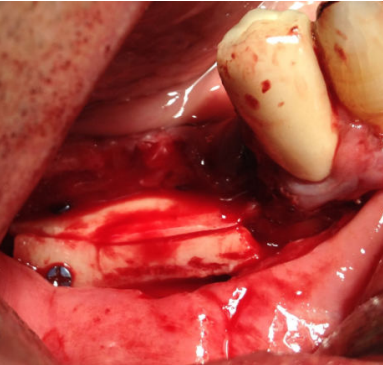

El injerto en bloque obtenido se dividió con la ayuda de un disco de corte en dos láminas corticales de 1,5 mm (Figura 4). Seguidamente, se fijó una de las láminas en la parte coronal del defecto óseo, creando un espacio virtual en altura de aproximadamente 6 mm que se rellenó con las partículas de hueso autógeno obtenidas (Figura 5). La lámina remanente se posicionó y fijó conformando la pared vestibular del defecto (Figura 6). La sutura se llevó a cabo mediante puntos de colchonero, favoreciendo así la cicatrización, y se utilizó monofilamento de 5/0. El CBCT postquirúrgico de control mostró una correcta reconstrucción tridimensional del defecto y el postoperatorio cursó con normalidad, sin signos infecciosos ni dehiscencias de la herida y sin alteraciones sensitivas (Figura 7).